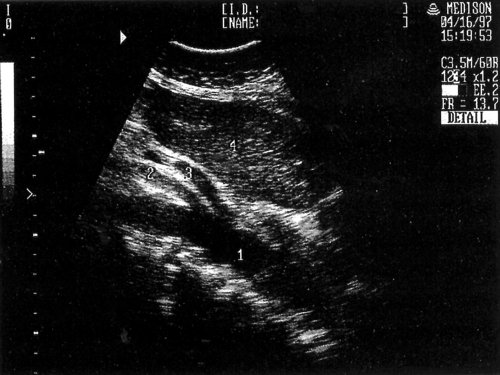

Рис. 8. Эхографическая картина порто-кавальных анастомозов в воротах печени: 1 - печень, 2 - желчный пузырь, 3 - порто-кавальные анастомозы, 4 - киста печени.